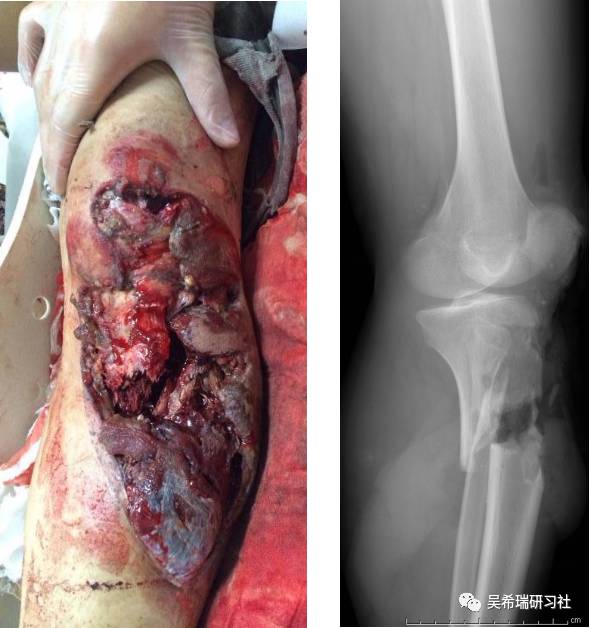

病例13

手术后40天外地转来胫骨外露感染骨坏死20cm胫前皮肤缺损腘动脉断裂腓总神经损伤足下垂

TIPS:第一次手术  清除病灶抗生素骨水泥填塞。远端整块水泥包裹外露骨质,近端连珠以便骨搬移钢丝克氏针张力缝合皮肤5天后下地部分负重走路联合骨牵引纠正足下垂15天后去除跟骨骨牵引针